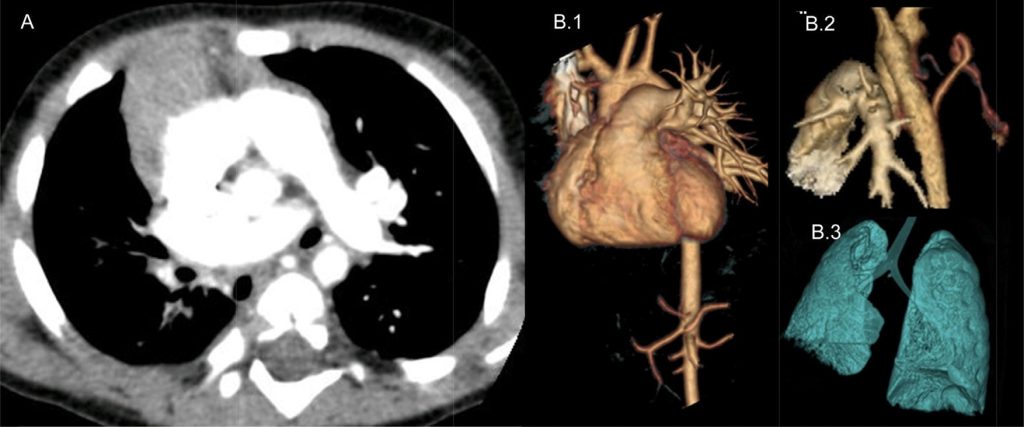

Diagnosis is often made during infancy or childhood, but some cases are only discovered incidentally in adults through imaging tests.

✔ CT Scan or MRI – Provides detailed imaging of the chest and confirms lung absence.